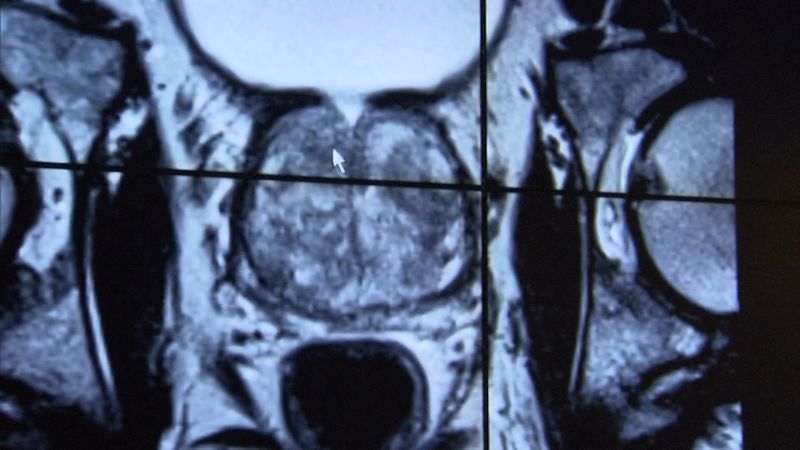

No es una conversación fácil de tener para los hombres, pero hablar de los problemas de la próstata es una parte crítica para mantenerse saludable. Los síntomas como la frecuencia urinaria, la urgencia o dificultad para ir al baño son una señal de una condición médica, y la demora en un diagnóstico puede llevar a un sufrimiento innecesario.